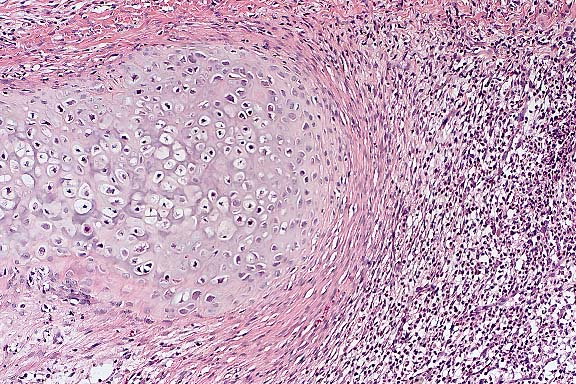

Case 27-2. Ear. Proliferating cartilage is surrounded by dense fibrous tissue and a loose infiltrate of neutrophils within and between the expanded mature collagen fibers. 10X

Contributor's Diagnosis and Comments: External ear: Inflammation, pyogranulomatous with cartilaginous proliferation and osseous metaplasia, severe, compatible with auricular chondropathy of Crl:CDÒ Rats.

The signalment, history and morphology of this case are consistent with the spontaneous auricular chondropathy of aging Sprague-Dawley and fawn hooded rats. The condition is characterized by degeneration and lysis of the auricular cartilage with associated granulomatous inflammation and subsequent cartilage hyperplasia and osseous metaplasia. This lesion has been compared to relapsing polychondritis in humans; however, in rats the lesion is limited to the ear.